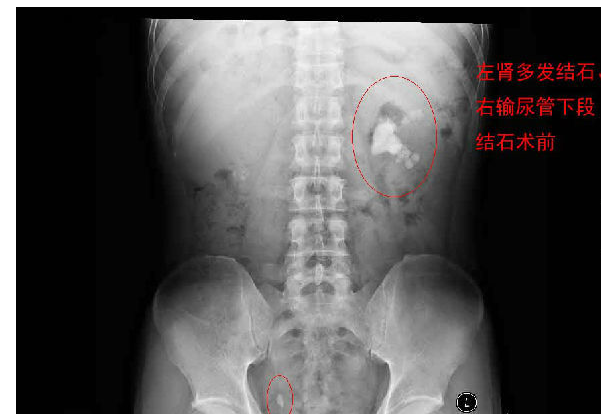

每天早上手術(shù)間響起泌外醫(yī)生們特有的交談聲音和機(jī)器們互相的運(yùn)轉(zhuǎn)聲交替成了一道熟悉不變的旋律,從手術(shù)室護(hù)士擺著各種專用體位,推著各種器械,液體進(jìn)進(jìn)出出,醫(yī)生們應(yīng)用著各種碎石手段消滅石頭,利用氣壓彈道、激光、超聲等碎石工具,把結(jié)石擊碎取出,一陣忙碌的節(jié)奏。泌尿外科的手術(shù)時(shí)間都不長,每天手術(shù)例數(shù)又多,你就會(huì)看見這么一群人來來回回,醫(yī)生護(hù)士還是那么個(gè),病人都換了無數(shù)。最長一次從早上8點(diǎn)到隔天凌晨2點(diǎn)才結(jié)束手術(shù),回到家就立馬睡覺都顧不上吃飯?,F(xiàn)在手術(shù)間正做著一臺(tái)經(jīng)皮腎鏡下碎石取石術(shù),這是我們醫(yī)院泌外科的王牌。

經(jīng)皮腎鏡取石術(shù),就是在腰部建立一條從皮膚到腎臟的通道,通過這個(gè)通道把腎鏡插入腎臟,英文簡寫為PCNL。經(jīng)皮腎鏡取石術(shù)是腎結(jié)石治療的現(xiàn)代微創(chuàng)技術(shù),我院在惠州率先開展此項(xiàng)技術(shù),現(xiàn)在每年進(jìn)行數(shù)百例手術(shù),基本上已經(jīng)淘汰了開放手術(shù)取石。經(jīng)皮腎鏡取石術(shù)是一項(xiàng)技術(shù)性非常強(qiáng)的手術(shù)。我們知道,腎臟是血管非常豐富的器官,腎臟血流占心臟排出血量的1/4。既要盡量避免出血、又要努力取凈結(jié)石、還要保護(hù)腎臟功能,這需要非常精細(xì)的手術(shù)技術(shù)。從某種程度上說,這個(gè)手術(shù)要比治療腎癌的腎切除術(shù)難度大很多。傳統(tǒng)的“開刀取石”的方法,需要在腰部做一個(gè)的大切口,切開腰部的肌肉,把腎臟分離出來,在腎盂或腎實(shí)質(zhì)切開一個(gè)小口,將結(jié)石取出來。這種方法損傷大、出血較多、痛苦重、恢復(fù)慢。通常手術(shù)后需要住院7天以上。因?yàn)槭中g(shù)切口大,不但皮膚不美觀,而且手術(shù)后患者的體力受影響比較大。與開放手術(shù)相比,經(jīng)皮腎鏡取石術(shù)具有損傷小、痛苦輕、取石徹底、恢復(fù)快等優(yōu)點(diǎn)。腰部的切口通常小,因?yàn)椴磺虚_肌肉,不但不影響美觀,而且手術(shù)后對勞動(dòng)力幾乎沒有影響。手術(shù)后住院時(shí)間也明顯縮短。與腹腔鏡取石相比,經(jīng)皮腎鏡取石術(shù)對腎臟及周圍的結(jié)構(gòu)影響小,不影響以后的各種腎臟手術(shù)。與體外碎石相比,它的治療周期短、效果立竿見影,對腎功能的影響也較小。(手術(shù)室/麻醉科 阮伊莎)